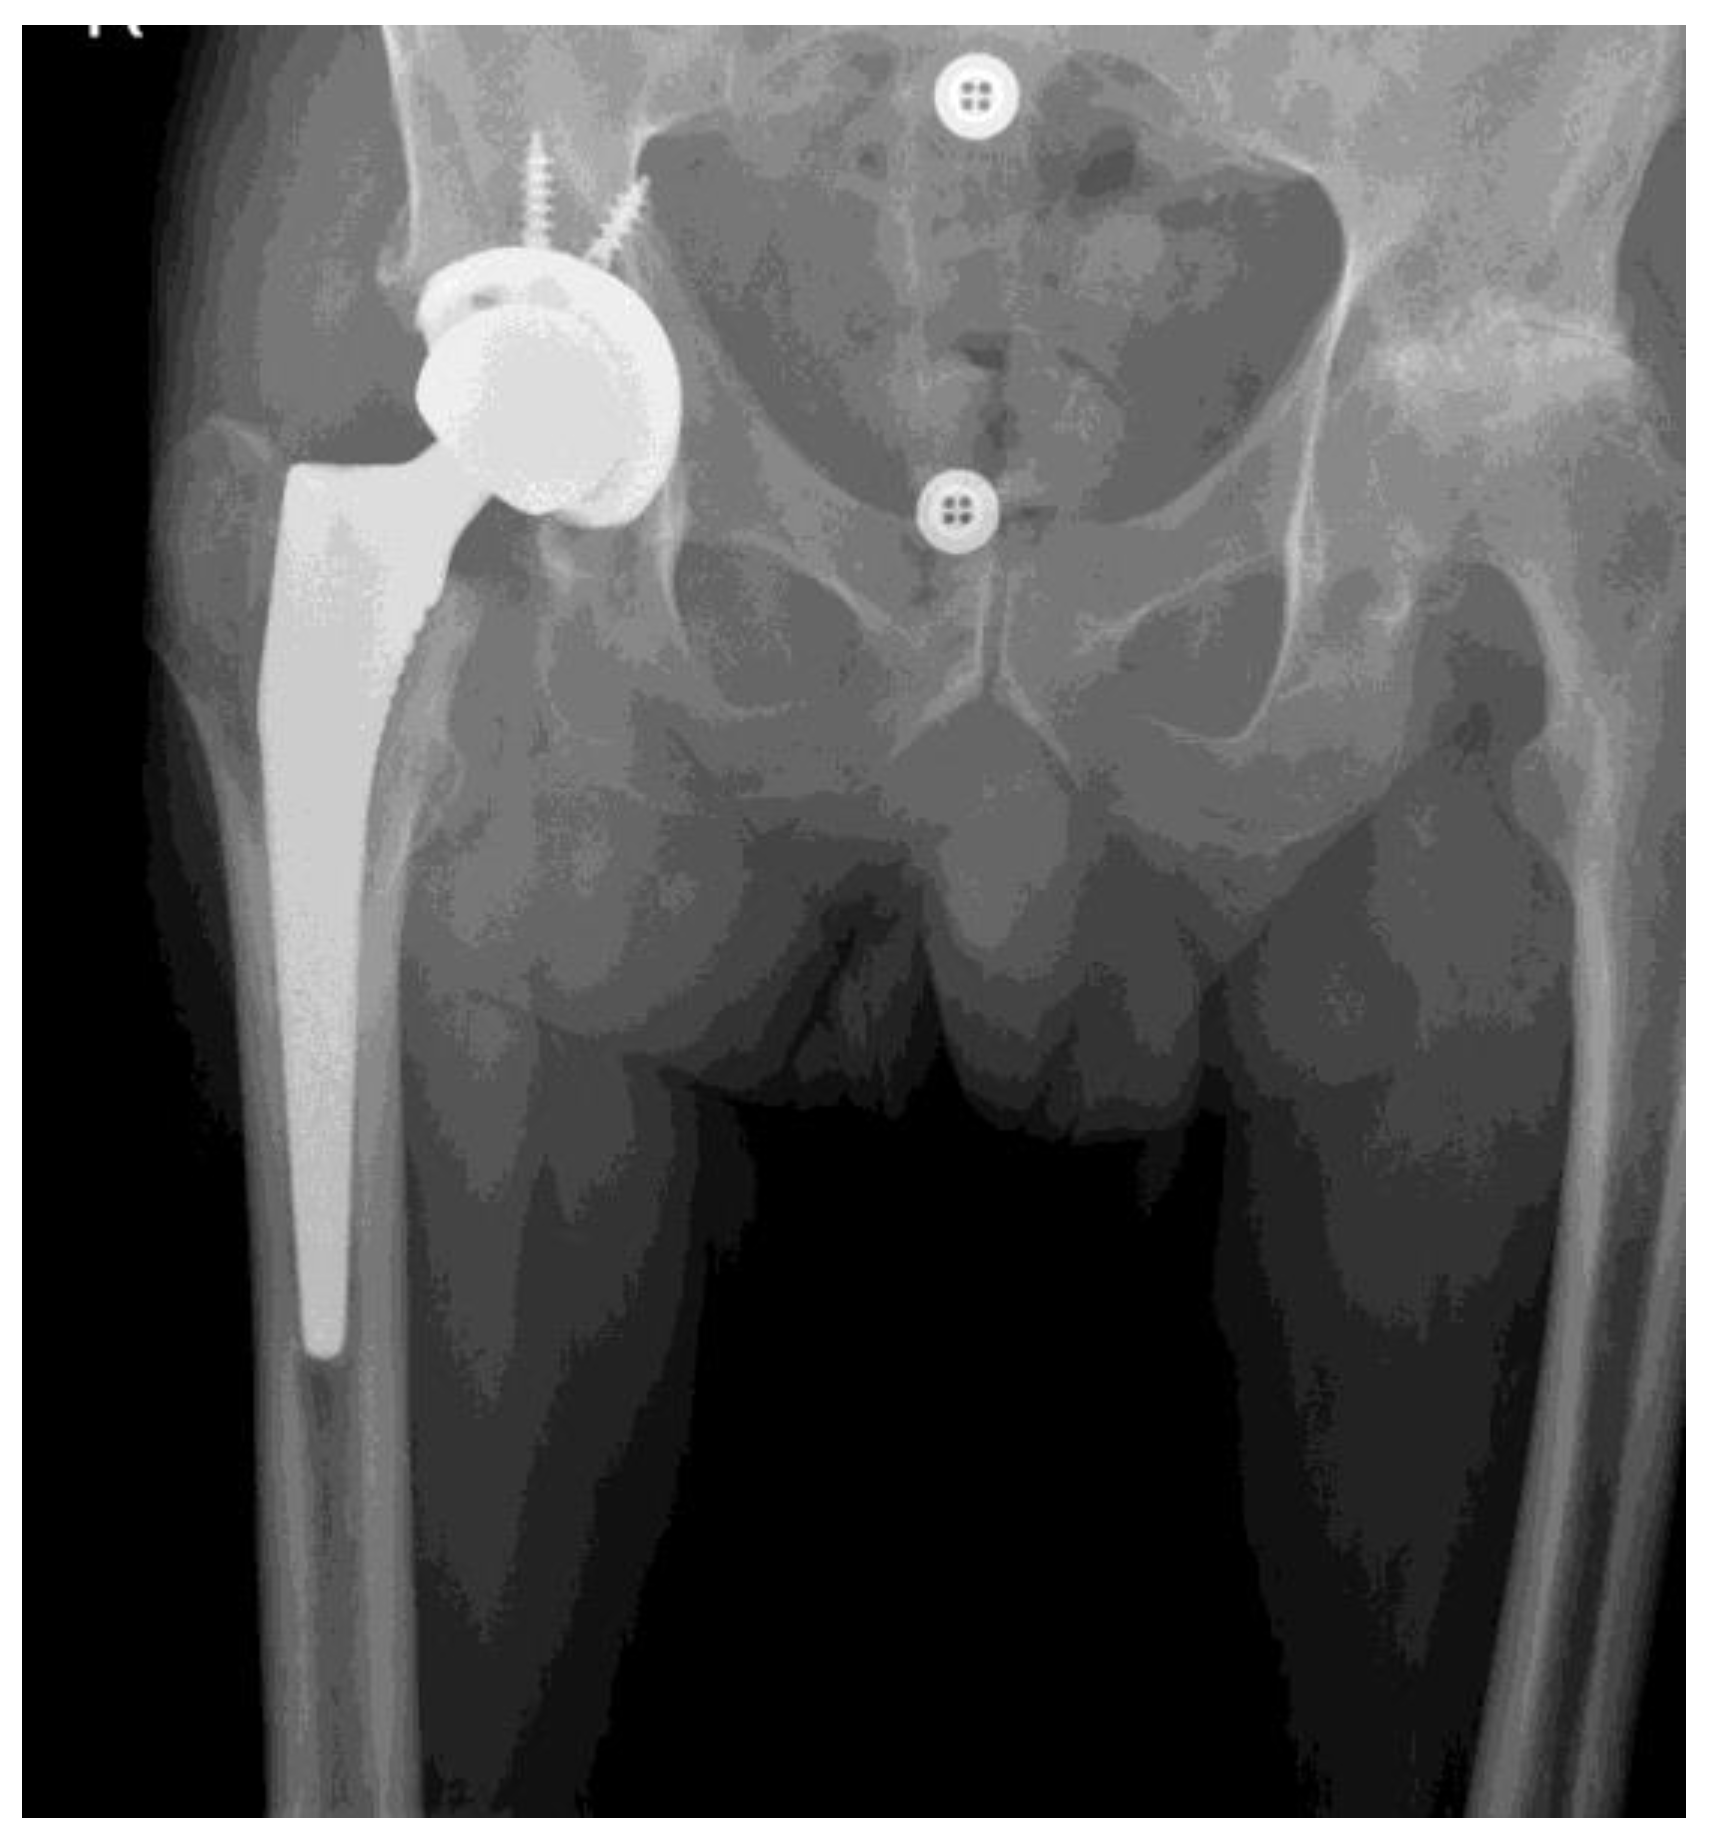

*Level of Disability after Total Hip Replacement in Patients with *